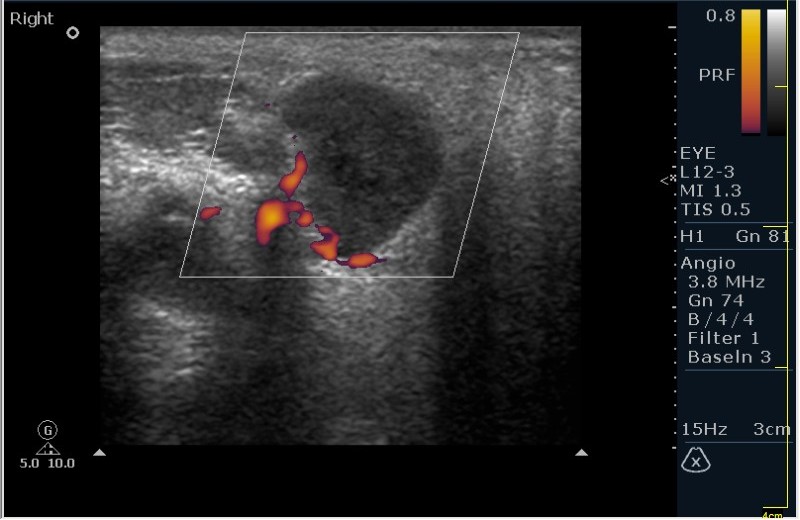

Мужчина 68 лет, направлен на УЗИ правой слюнной железы. Жалобы на пальпируемое, малоболезненное плотное образование за правым ухом.

Солидное!!!! Я тоже ТАБ хотел сделать, но ЛОР заказал КТ... А какие мысли будут?

Первая мысль о очаговом воспалении, деструктивной фазе, но нет клиники.

Тумор?

Клиники нет, тумор на первом месте. В принципе КТ (или МРТ) заказывают для диффиренцировки зло/добро. Плюс посмотреть есть ли локальное растпространение. Но в данном случае я думаю УЗИ с ТАБ было бы достаточно.

Согласен! Поэтому в КТ отказал и настоял на ТАБ. Итак? Варианты?